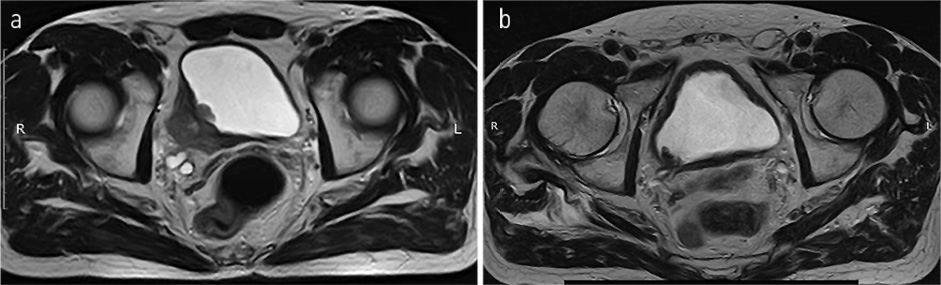

В июне 2022 г. выполнено контрольное обследование, МРТ ОМТ: на полученных МРТ в сравнении с обследованием от 24.03.2022 без существенной динамики. Пациент оставлен на МХТ препаратом этопозид (рис. 6).

Рис. 6. МРТ ОМТ от 07.06.2022. Состояние после 6-го курса лекарственного лечения по схеме EP. Cостояние в процессе МХТ препаратом этопозид.

Fig. 6. Pelvic MRI dated 07.06.2022. State after the 6th course of drug treatment according to the EP regimen. Monochemotherapy with etoposide is ongoing.

По результатам контрольного обследования от августа 2022 г. (МРТ ОМТ от 18.08.2022): в сравнении с данными от 07.06.2022 отмечается картина отрицательной динамики в отношении появления по задне-правой стенке мочевого пузыря на расстоянии до 11 мм от уретры узлового образования округлой формы с бугристыми контурами, с истинным ограничением диффузии и интенсивным контрастированием, размерами до 6×6 мм; характер роста образования смешанный; наружный контур стенки четкий ровный (рис. 7).

Рис. 7. МРТ ОМТ от 07.06.2022 в сравнении с МРТ ОМТ от 18.08.2022. Состояние после 6-го курса лекарственного лечения по схеме EP. Cостояние в процессе МХТ препаратом этопозид: появление узлового образования округлой формы с бугристыми контурами.

Fig. 7. Pelvic MRI dated 07.06.2022 in comparison with pelvic MRI dated 18.08.2022. State after the 6th course of drug treatment according to the EP regimen. MCT with etoposide is ongoing. A rounded nodule with bulging contour appeared.

С 08.2022 начал получать полихимиотерапию (ПХТ) по схеме: карбоплатин + иринотекан. По данным контрольного обследования 18.08.2022 отрицательная динамика в виде увеличения размеров метастатических очагов в костях таза, наибольшими размерами в левой подвздошной кости на уровне тазобедренного сустава до 25×23 мм (ранее до 17×15 мм), в крыле правой подвздошной кости до 36×18 мм (ранее до 15×7 мм), в боковой массе крестца слева до 24×26 мм (ранее до 18×14 мм); рис. 8. Обсужден на консилиуме №91016 от 09.11.2022, рекомендовано: проведение паллиативной лучевой терапии последовательно на область правой и левой половины таза в разовой очаговой дозе (РОД) 6,5 Гр до суммарной очаговой дозы (СОД) 26 Гр.

Рис. 8. МРТ ОМТ от 18.08.2022 в сравнении КТ ОМТ от 02.11.2022. Состояние после 3 курсов лекарственного лечения по схеме карбоплатин + иринотекан.

Fig. 8. Pelvic MRI dated 18.08.2022 in comparison with pelvic CT dated 02.11.2022. State after 3 courses of drug treatment with carboplatin + irinotecan.